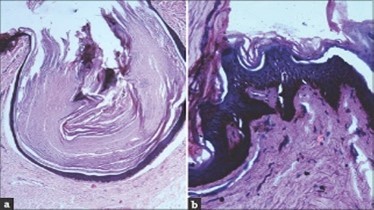

A cogent tissue specimen demonstrates typical features of comedones as follicular ostia distended and impacted with keratin. Significant histological manifestations are the occurrence of enlarged, grouped, distended follicular ostia demonstrating an absence of hair shafts along with impaction of laminated keratin. Base of the follicular invaginations may or may not delineate singular, rudimentary glandular structures. Miniature cysts, cystic invaginations and occasional enlarged cysts can be encountered. Cystic articulations are diverse and preponderantly layered by keratinizing, stratified squamous epithelium. Hyperkeratosis or epidermolytic hyperkeratosis and acanthosis of superimposed epidermis can concur although the lesion is devoid of parakeratosis or dyskeratosis5, 6.

Nevus comedonicus demonstrates immune reactivity to cytokeratin, simulating the expression of normal cutaneous surfaces. Generally encountered within the granular epidermal layer, immune reactivity for filaggrin is demonstrable within the entire epidermal thickness of closed comedones, a molecular which can be implicated in the genesis of nevus comedonicus6, 7. Electron microscopy demonstrates an enhanced quantification of Langerhans cells, numerous kerato-hyaline granules along with an abundance of tonofilaments within upper portion of stratum spinosum. Incompletely differentiated arrector pili muscles are impacted with intracellular glycogen particles6, 7. Figure 1, Figure 2, Figure 3, Figure 4, Figure 5, Figure 6, Figure 7, Figure 8, Figure 9, Figure 10.

Figure 1.Nevus comedonicus with grouped, dilated follicular ostia, impacted with keratin and a layering of hyperkeratotic stratified squamous epithelium11.

Figure 2.Nevus comedonicus with plugging of follicular ostia, keratinous impaction and a lining of hyperkeratotic stratified squamous epithelium11.

Figure 3.Nevus comedonicus with aggregated follicular ostia, lamellated keratin, hyperkeratotic stratified squamous epithelial lining and an attenuated superimposed epithelium12.

Figure 4.Nevus comedonicus with distended follicular ostia, keratin accumulation, hyperkeratotic epithelial lining and intervening loose fibro-connective tissue13.